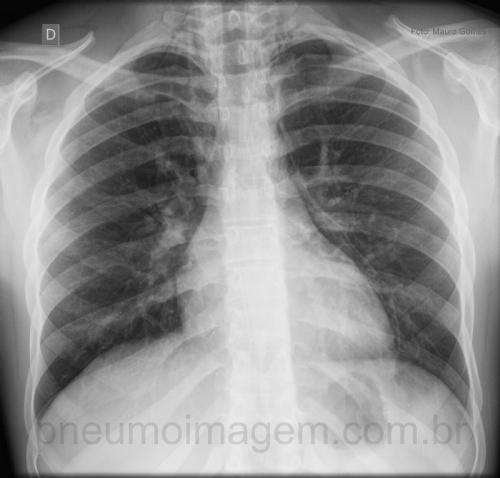

CASO CLÍNICO #2Jovem do sexo masculino, 16 anos de idade, asmático leve sem tratamento regular, apresenta-se com intensa dispneia e dor torácica que se iniciou enquanto disputava uma partida de futebol. Qual o diagnóstico? Observe a imagem e deixe os seus comentários abaixo.

Young male, 16 years-old, mild asthmatic patient without regular treatment, presented with severe dyspnea and chest pain that began while disputing a soccer match. What is the diagnosis? Observe the image and leave your comments below.

Pneumomediastinum, Pneumopericardium

Pneumomediatinum

Pneumomediastino com enfisema sub-cutâneo

Pneumomediastino / Pneumopericárdio